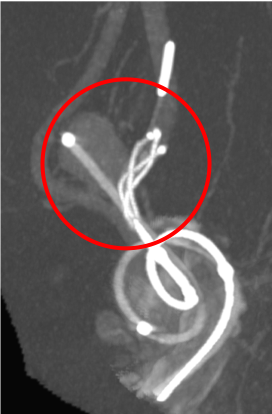

フローダイバーターステント留置術

通常のコイル塞栓術では不完全閉塞になりやすく、また再発の可能性が高いと考えられる大型の脳動脈瘤に対しては『フローダイバーターステント』を用いた治療を行います。

近年、中型の脳動脈瘤に対しても『フローダイバーターステント』での治療も行っております。

術前の造影写真です。〇内に脳動脈瘤が造影されています。

術直後の造影写真ではまだ脳動脈瘤は造影されています。

術直後の写真です。〇内は留置されたフローダイバーターステントです。

半年後の造影写真では脳動脈瘤は完全に消失しています。